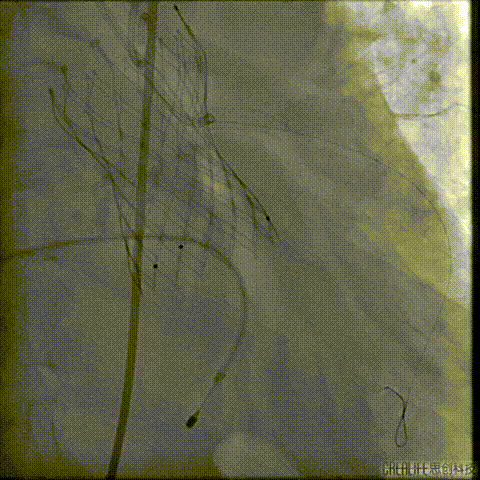

预扩主动脉瓣

左冠血流受到影响

予ECOM支持

患者恢复自主心率

经桡冠脉保护